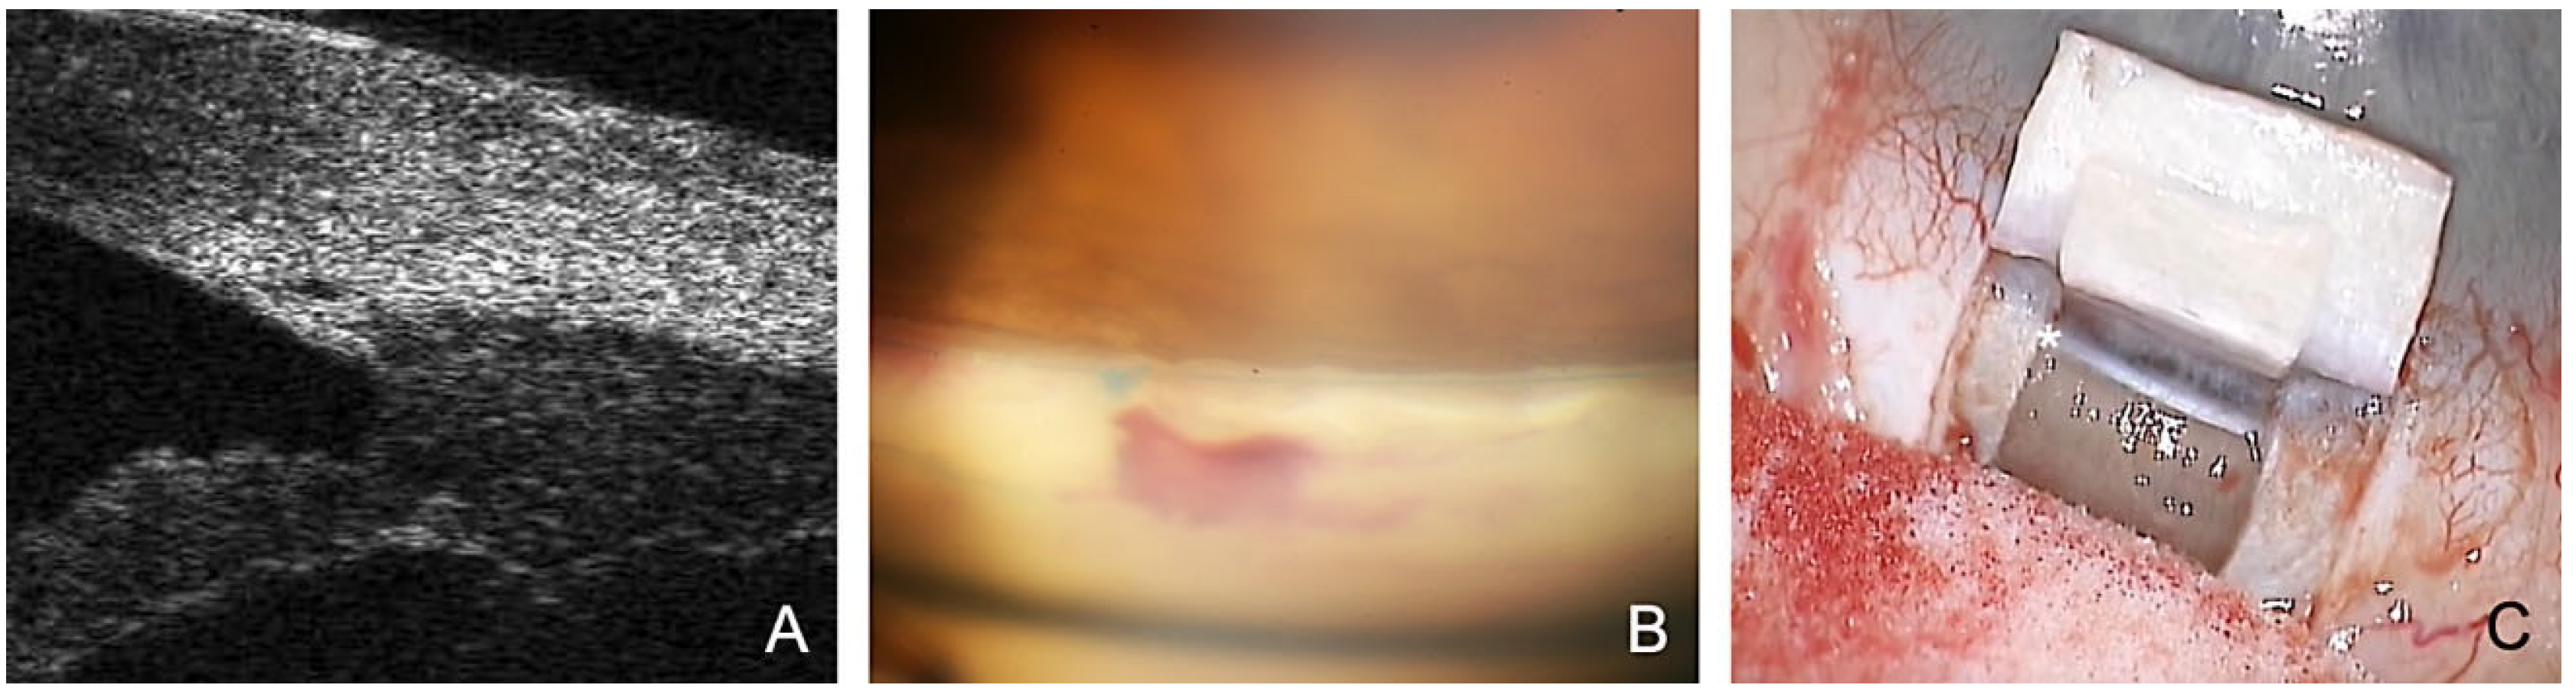

- The SC is probed using a microcatheter (iTrack 250, Ellex Inc., Eden Prairie, MN, USA) for dilatation of the ostia and lumen of SC, and the adjacent collector channels using a viscoelastic. This effect dilates the canal to almost triple its original size, making it easily visible in the ultrasound biomicroscope (UBM) 50 MHz (Figure 1A).

- Applying tension to the TDW results in the controlled percolation of aqueous humor into the intrascleral cleft formed after resection of the deep flap, which can be enhanced by YAG goniopuncture [13].